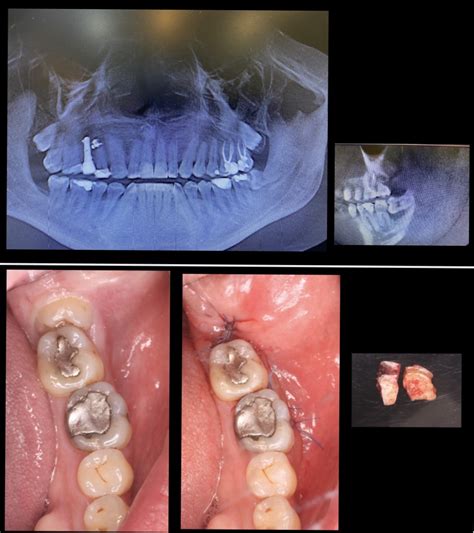

- Radiografía Previa: Lo primero que se debe hacer es una radiografía de la zona, para así captar todos los dientes y obtener los detalles de esta.